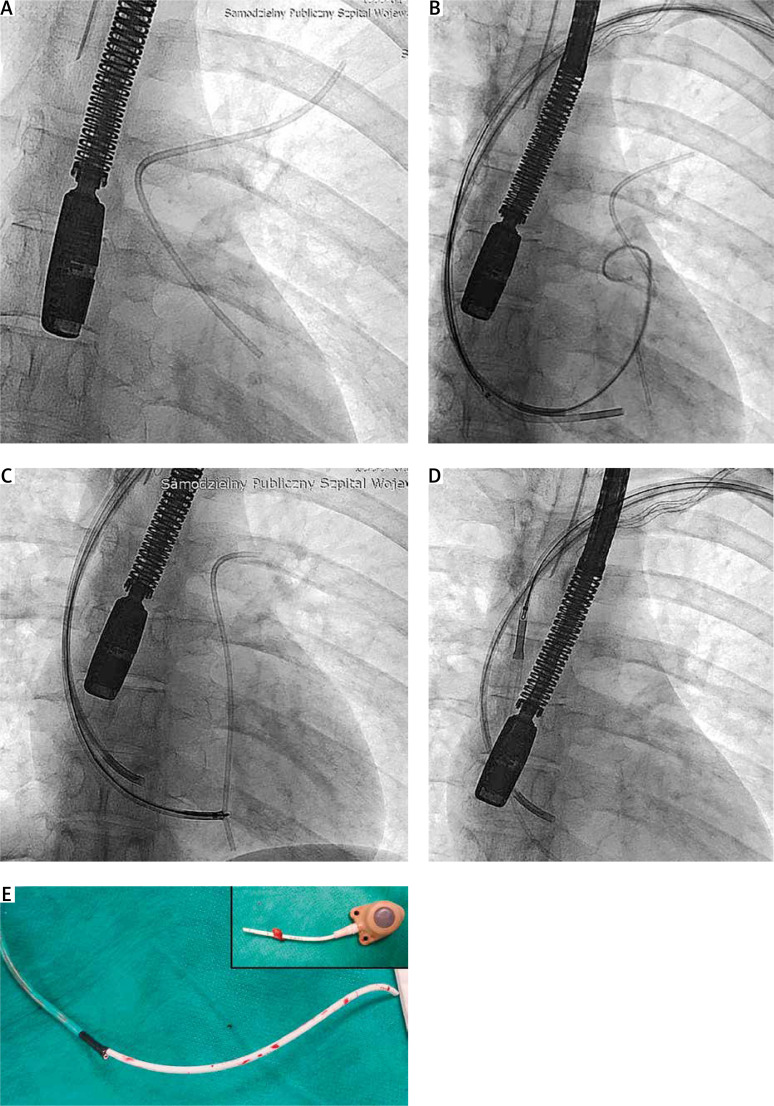

The use of venous access ports carries a risk of complications, including catheter fracture with migration of catheter fragments into the pulmonary arteries. Experience in removing broken catheters is limited and there are no special tools. We present 4 cases of catheter removal using the available lassos/lasso catheter and tools designed for transvenous lead extraction and coronary sinus lead implantation via a femoral and subclavian approach. All four procedures were successful and without complications.